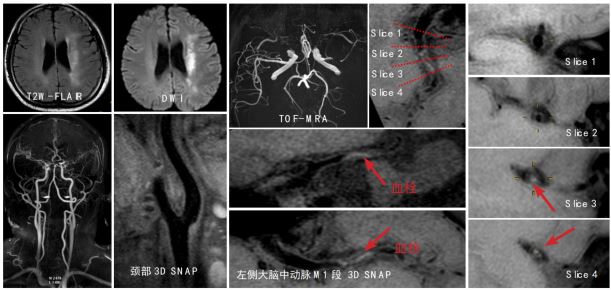

高分辨血管壁成像技术清晰显示椎动脉及基底动脉粥样硬化并斑块形成至管腔狭窄 磁共振高分辨血管壁成像技术显示左侧大脑中动脉 M1 段内血栓致左侧大脑梗塞

磁共振高分辨血管壁成像技术清晰显示左侧大脑中动脉 M1 段炎性增强及管腔狭窄 左侧颈内动脉路外段动脉夹层,可观察到真假腔、内膜片和周围炎性渗出 磁共振大范围高分辨血管壁多对比度成像技术